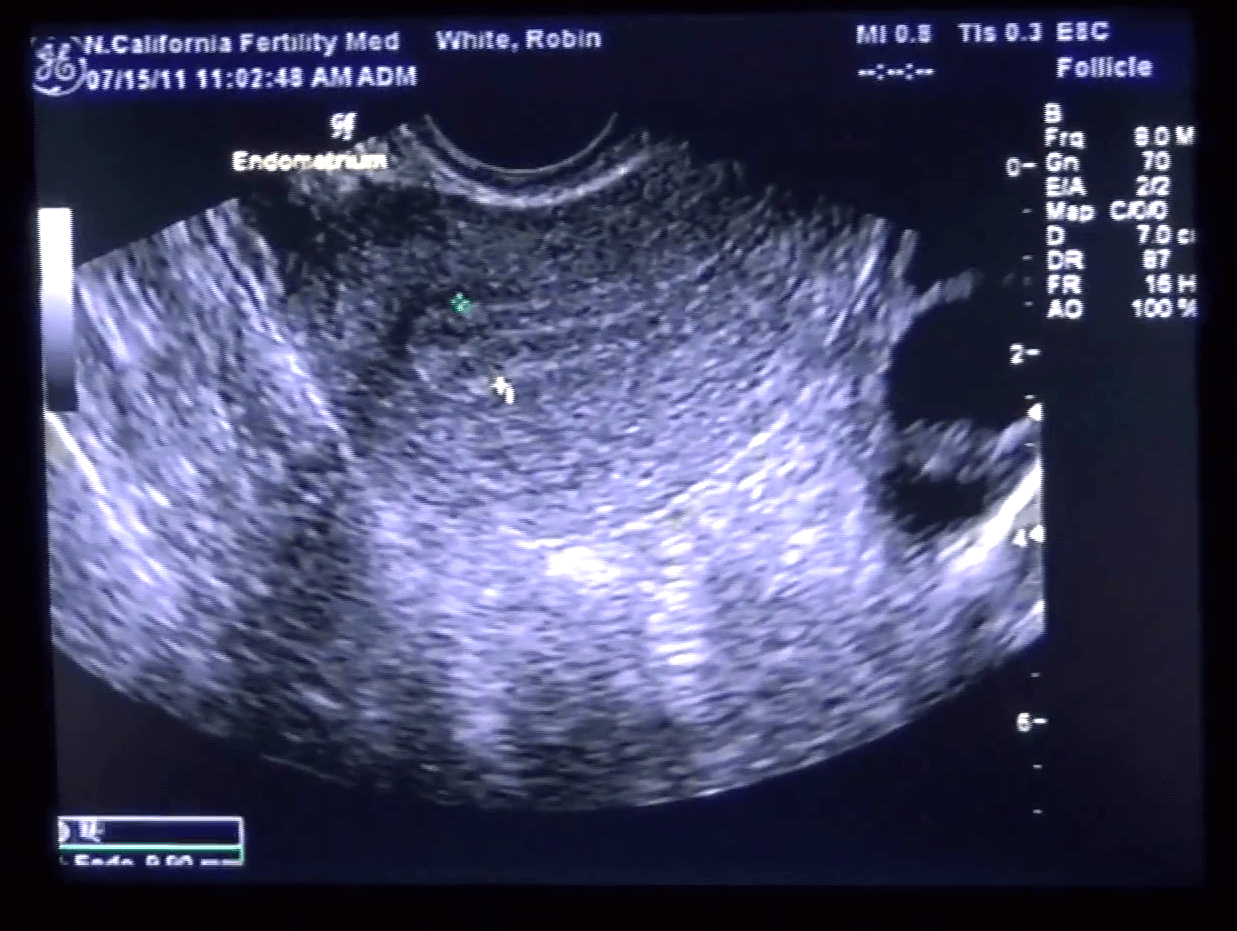

Endomètre épais 20 Mm Forum. Changements de l'endomètre au cours du cycle menstruel Bonjour les filles,au lieu d'avoir l'endometre fin et bien moi il est trés epais ,dernier jour de stim avec 300 u de menopur et aujourd'hui à l'echo mon endometre mesure 20 mm et je sais que c. L'endomètre épais chez les femmes ménopausées peut être préoccupant, mais il est important de savoir qu'il existe des solutions et des traitements disponibles

Consulter Masquer le sommaireLes causes de l'épaississement anormal de l'endomètreSymptômes de la muqueuse utérine épaisseComment traiter l'épaississement anormal de l'endomètre ?Prévenir l'hypertrophie endométrialeLe cancer de l'endomètre peut être envisagéChez la femme non ménopausée, le cycle mensuel se divise en deux parties Bonjour les filles,au lieu d'avoir l'endometre fin et bien moi il est trés epais ,dernier jour de stim avec 300 u de menopur et aujourd'hui à l'echo mon endometre mesure 20 mm et je sais que c.

Le monitorage des ovaires. Mon gyne me prescrit une prise de sang hormonal et une biopsie et hystero la semaine pro. Sur le forum de fiv.fr échangez librement sur tous les sujets liés à la PMA, FIV et PMA à l'étranger ! Question taille endomètre- endomètre épais help! - Le forum de la FIV, Insémination et de la PMA